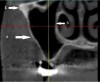

Fig 5. Anterior loop of the mental foramen: six consecutive cross-sectional views. Sections anterior to the mental foramen demonstrate a radiolucency that corresponds to the loop of the inferior alveolar nerve. In these cross-sections, the anterior loop has a “C” shape due to the cut of the images (arrow). Therefore, immediately above the loop, an implant longer than the safety zone (distance from the alveolar ridge to the mental foramen minus 2 mm for safety) should not be placed.

Figure 5